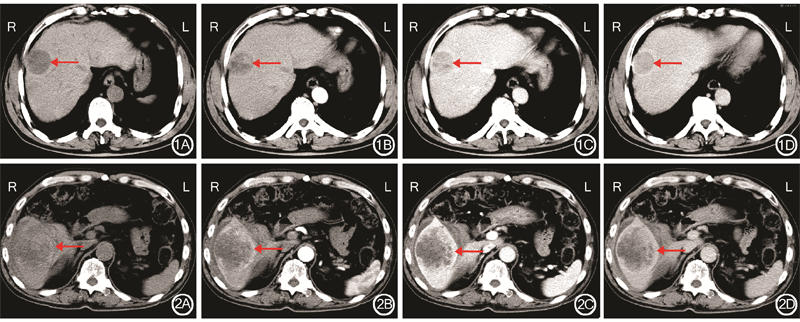

(2)肿瘤病理学检查结果显示:8例病人瘤细胞长梭形、核梭形、卵圆形,核分裂易见,瘤细胞呈束状及编织状排列。①2例肿瘤分化为Ⅰ级(低度恶性):肿瘤细胞少,有丝分裂较少,含丰富胶原纤维,与纤维样瘤近似,肿瘤细胞分化好。CT平扫检查示肿瘤膨胀性生长,均匀略低密度,界限清晰;增强扫描检查动脉期示瘤周环状轻度强化,门静脉期示持续强化,延迟期示强化缓慢退出(图1)。②5例肿瘤分化为Ⅱ级和Ⅲ级(中度恶性):肿瘤细胞表现界于Ⅰ级与Ⅳ级之间。CT平扫检查示肿瘤膨胀性生长,肿瘤呈均匀或不均匀低密度,界限清晰或不清晰,瘤内可见坏死、囊变;增强扫描检查动脉期示肿瘤呈不均匀中度强化,瘤内可有或无条状强化血管,门静脉期示强化降低或持续强化,延迟期示强化退出。③1例肿瘤分化为Ⅳ级(高度恶性):肿瘤细胞多,高度间变,有丝分裂多,胶原纤维少,分化差。CT平扫检查示肿瘤浸润性生长,不均匀低密度,界限不清晰,瘤内见片状坏死、囊变区;增强扫描检查动脉期示肿瘤呈不均匀显著强化,瘤内见条状强化血管,门静脉期示强化明显降低,延迟期示肿瘤强化退出(图2)。

(3)CT增强扫描检查结果显示:①8例病人CT增强扫描检查动脉期示肿瘤呈不均匀强化,CT值为68 HU(44~73 HU),其中4例瘤内呈条状强化血管,2例呈环形强化,2例瘤周呈结节状强化;3例显著强化,3例中度强化,2例轻度强化。②8例病人CT增强扫描检查门静脉期示肿瘤密度不均匀,CT值为62 HU(50~65 HU),其中3例瘤内见小片状或网格样持续中度强化,3例强化明显降低,2例强化轻度降低。③8例病人CT增强扫描检查延迟期示肿瘤强化均缓慢退出,密度低于肝实质,CT值为53 HU(50~60 HU)。

(2)CT平扫检查结果显示:8例病人肿瘤均呈低密度,CT值为40 HU(29~43 HU),其中密度不均匀6例,密度均匀2例;肿瘤呈膨胀性生长界限清晰6例,肿瘤呈浸润性生长界限不清晰2例;瘤内坏死、囊变5例,瘤内条片状出血灶2例,瘤内小片状钙化1例;肝门区淋巴结转移1例。

(1)肿瘤部位和大体观:8例病人肿瘤均为单发,肿瘤位于肝右叶6例,肝左叶2例;肿瘤呈椭圆形5例,圆形3例;肿瘤长径为9.3 cm(4.0~15.0 cm),其中长径≤5.0 cm 1例,5.1~10. 0 cm 4例,>10.0 cm 3例。